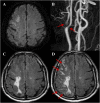

Purpose: The hyperintense acute reperfusion marker (HARM) is a delayed enhancement of the subarachnoid or subpial space observed on post-contrast fluid-attenuated inversion recovery (FLAIR) images and is associated with permeability changes to the blood-brain barrier in acute stroke. We investigated the relationship between HARM and stroke etiology based on the Trial of ORG 10172 in Acute Stroke Treatment (TOAST) classification. In addition, we evaluated the relationship between HARM and stroke locations with respect to vascular territories and anatomic compartments.

Results: Among the 264 patients, 67 (25.38%) patients were HARM positive and 197 (74.62%) patients were HARM negative. There was significant difference in HARM incidence among the stroke subgroups (p < 0.001). Small vessel occlusion (SVO) was associated with the HARM-negative group (p < 0.001), while large artery atherosclerosis (LAA) and cardioembolism (CE) were associated with the HARM-positive group (p = 0.001). Also, regional pattern of HARM on the same vascular territory as the acute infarction was dominantly demonstrated regardless of stroke etiology. The OR for HARM from middle cerebral artery (MCA) infarction was 1.868 [95% confidence interval (CI): 1.025-3.401]. The OR for HARM from cortical infarction was 9.475 (95% CI: 4.754-18.883) compared to other anatomic compartments.

Conclusion: The presence of the HARM was significantly associated with embolic infarctions including LAA and CE. Conversely, SVO was exclusively associated with the absence of the HARM. Second, MCA and cortical infarction showed a more pronounced HARM compared to infarctions at other vascular territories and anatomic compartments. According to the results in the current study, we speculate that the presence of HARM on post-contrast FLAIR images was associated with specific stroke causes especially in embolic causes.